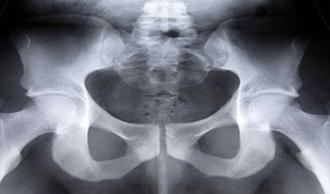

La cadera es una articulación compuesta de una superficie articular a modo de esfera y una cavidad. El borde de la cavidad está recubierto de un anillo de cartílago denominado labrum. Éste protege el hueso y ayuda a aislar la articulación. El desgarro de esta capa puede irritar la articulación de la cadera, producir dolor y limitar el movimiento.